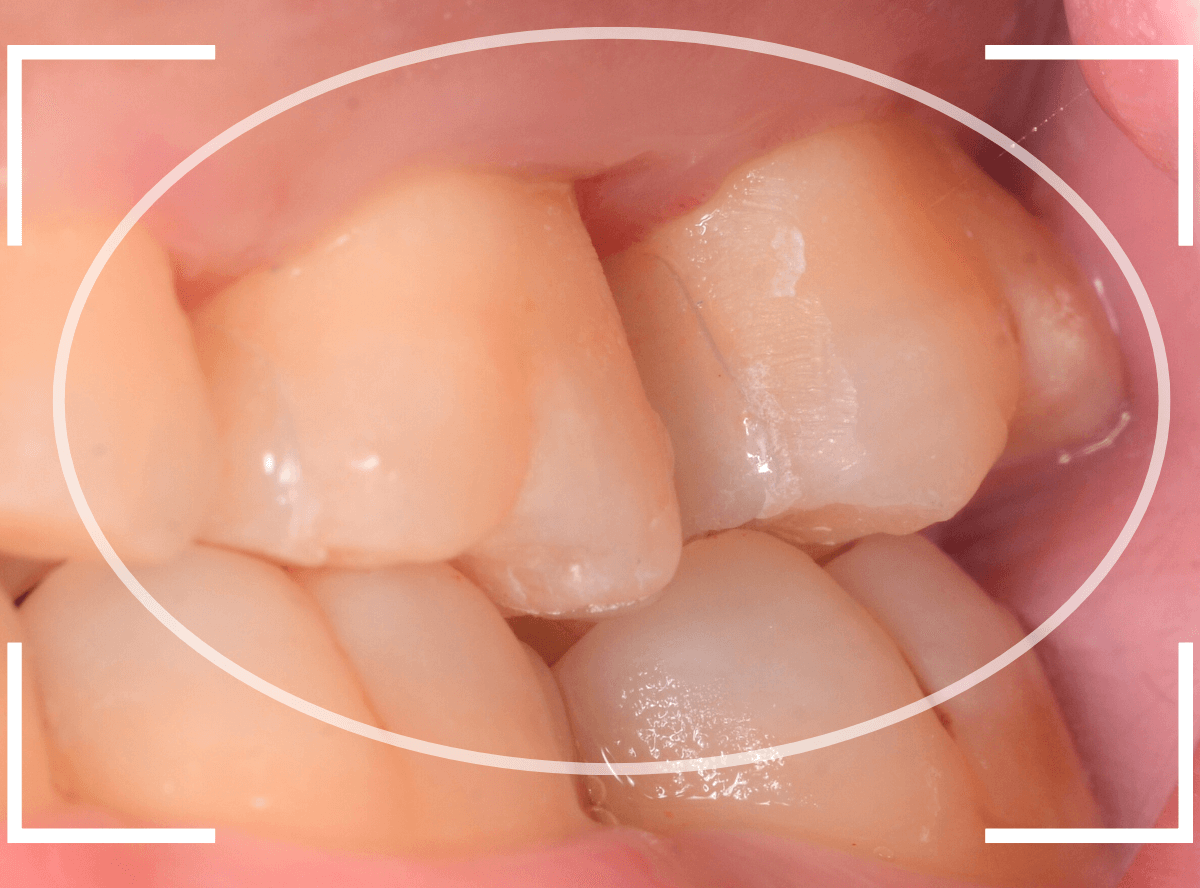

Case.29

舌のそばの虫歯とセラミック治療

下の奥歯が虫歯になった患者さんのケースです。

〇部が虫歯の部分です。

写真で見てわかるように、常に舌が歯に触っているような状況です。

このような場合、虫歯を見つけづらいですし、治療の難易度もあがります。